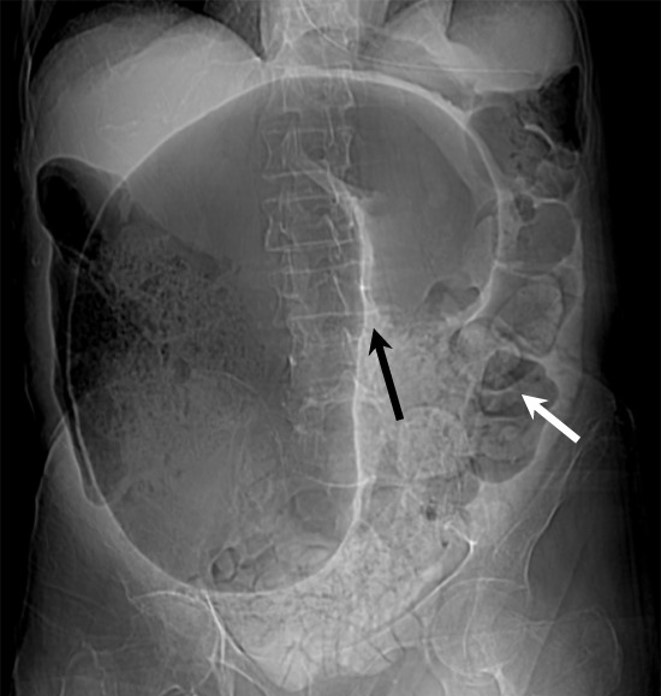

Just to look at and differentiate from a sigmoid volvulus

What are the 2 types of non-mechanical bowel obstruction ?